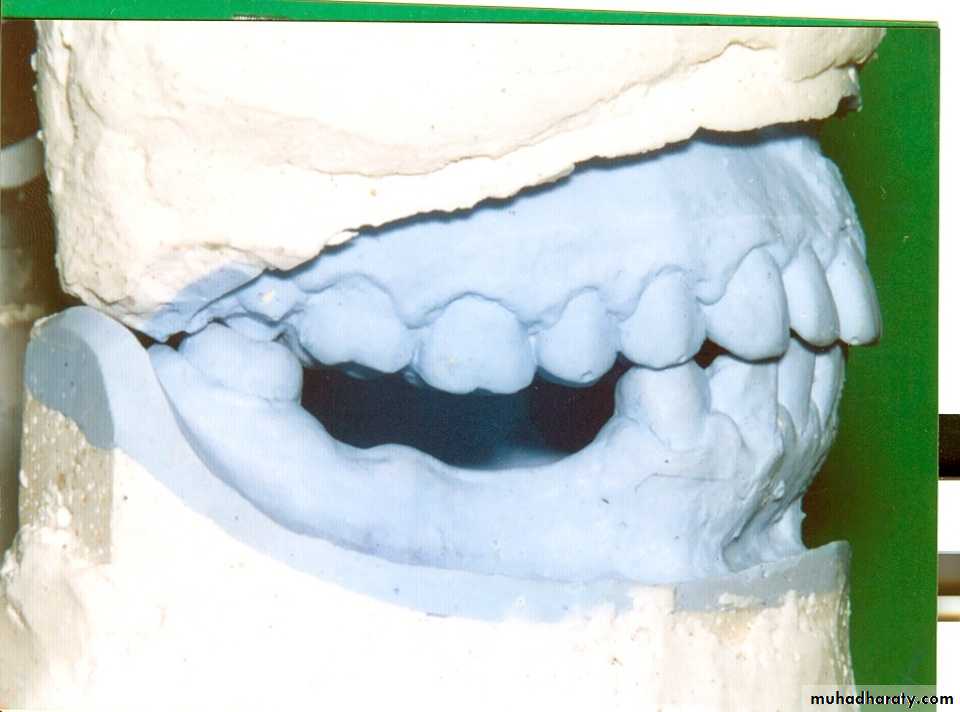

Telescopic Retainers

►A telescopic retainer consists of an inner coping. Permanently cemented to an abutment and a congruent detachable outer crown, rigidly connected to a removable prosthesis.

Definition of Telescopic Retainers

*Langer (1981) classified telescopic retainers ( according to resiliency) into:Rigidly interlocked T. Units

T. Units with built-in Resiliency

* involves intersurface friction

during insertion & removal of the superstructure as the parts engage & disengage themselves.

* The forms of the 1ry & 2ry crowns are modified to interrupt the continuity of the intimate contact between them. A stress breaking principle is built into the retainer itself.

* provide support only

Classification of Telescopic Retainers►ensures denture retention & stability.